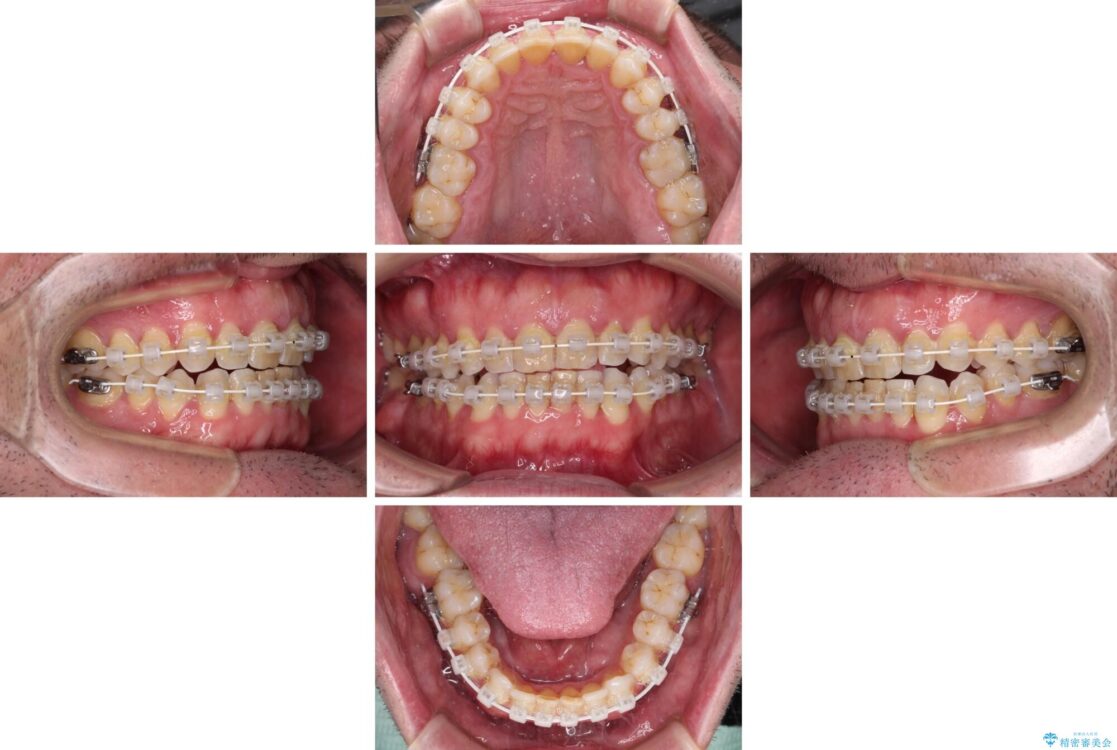

前歯の非接触改善は、インビザラインの得意とするところですが、マウスピース矯正は絶対に継続できないとのことで、ワイヤー装置にて矯正治療を行うこととしました。

治療途中